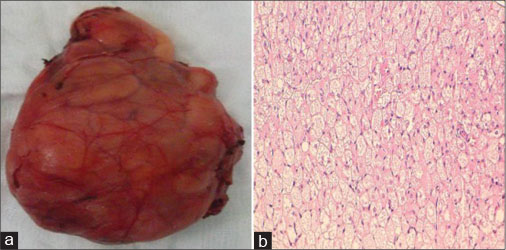

The mass was excised completely, and the defect was repaired in layers. Histopathological evaluation (HPE) confirmed the diagnosis of benign hibernoma. HPE showed the tumor to have a thick intact capsule consisting of collagenous connective tissue. On microscopy, abundant brown fat with a plenty of fat lobules separated by connective tissue septa was present. This was depicted by cells with granular deeply eosinophilic cytoplasm along with clear multivacuolated cells filled with lipid droplets [Figure 2a] and [Figure 2b]. The nuclei were small, regular, and round with no atypia and rare mitoses. Postoperative recovery was uneventful, and the patient was discharged on the 3rd?postoperative day. There was no recurrence after 1 year of follow up.

|?Fig. 2: (a) Gross specimen after complete excision, (b) microscopic histopathological evaluation of the excised specimen

The needle biopsy carries a risk of hemorrhage and often leads to inconclusive results; hence, the definitive diagnosis is based on histopathological analysis after surgical excision biopsy.[6] The microscopic examination of the tumor is characterized by cells of various degrees of differentiation. Usually, multivacuolar adipocytes and brown fat cells with granular eosinophilic cytoplasm are interspersed with univacuolar adipocytes.[1] The characteristic color of hibernoma is derived from the increased vascularity combined with abundant mitochondria.[1] Four histological variants of hibernoma have been described by Furlong?et al. [Table 1].[5]

|?Fig. 2: (a) Gross specimen after complete excision, (b) microscopic histopathological evaluation of the excised specimen